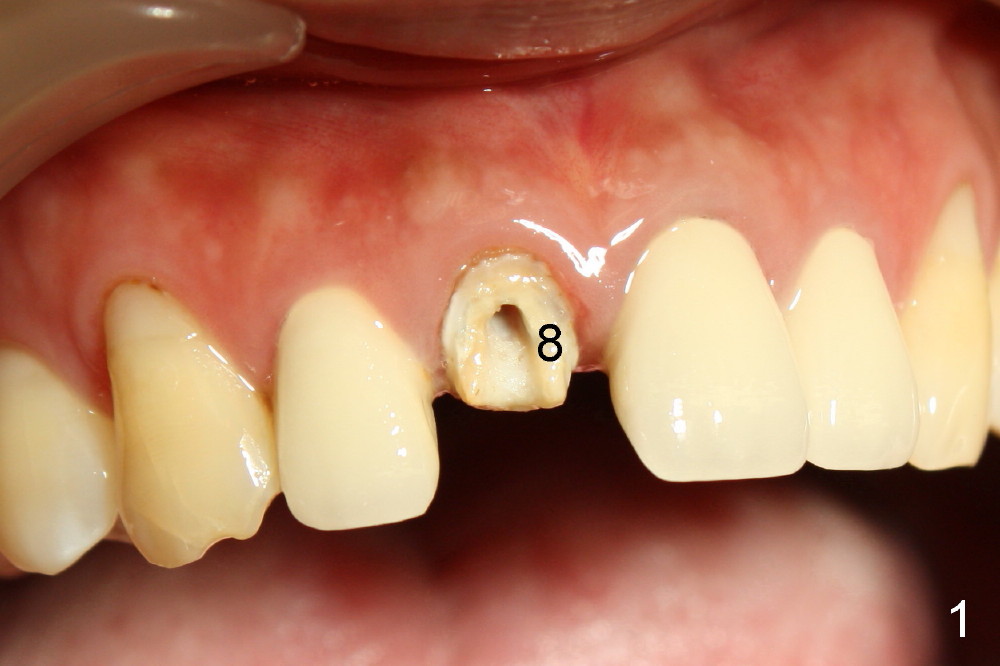

四十四岁女病人上颌中切牙突然断裂(图一:8),经过讨论,她同意植牙。由于根尖(图二黑线轮廓)上方骨头很多(箭头:鼻底),适合立刻植牙。牙根长度十一毫米左右,宽度约五毫米,准备植入直径五毫米植牙。拔牙后使用两毫米钻头,深度二十毫米(图三从颊侧牙龈缘算起),超过牙槽窝底部接近七毫米,所以植牙至少有七毫米新骨支持,将非常稳定。然后逐步使用2.5, 3.0, 和3.5毫米钻头,同一个深度,边钻边注意钻头(图四:D)近远中(图四)以及颊舌侧(图五)方向。